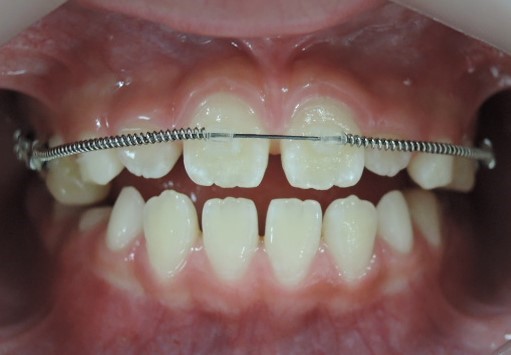

次にMEAW(マルチループ)を利用する事で咬み合わせの高さや咬み合う平面の角度を変える事で歯(第一小臼歯)を抜く事無く受け口(下顎前突)を改善していきます。

また、MEAW(マルチループ)はゴムを24時間使用する事で最大の効果を発揮することが出来ます。

その後、下顎にも矯正装置を装着して歯並びを綺麗にしていきます。

その後、MEAW(マルチループ)と顎間ゴムを24時間利用する事で受け口(下顎前突)と歯並びを改善していきます。